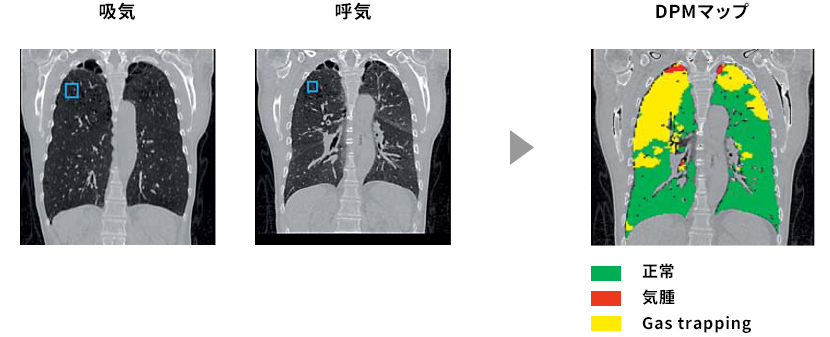

CTの吸気および呼気の画像解析によるDPM※9,1

DPMとは、吸気および呼気のCT画像におけるそれぞれのHU値から確率密度関数を用いて気腫とgas trappingが含まれる確率を計算し、マップ化したものである。

DPMは小気道病変や気腫の原因解明に有用である可能性が報告されている。

• ※9DPM:Disease Probability Measure、疾患確率測定